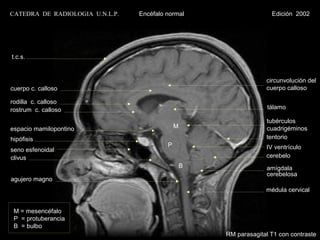

RM parasagital T1 con contraste

CATEDRA DE RADIOLOGIA U.N.L.P.   Encéfalo normal                     Edición 2002

t.c.s.

circunvolución del

cuerpo c. calloso                                                  cuerpo calloso

rodilla c. calloso

rostrum c. calloso                                                  tálamo

tubérculos

espacio mamilopontino                         M                    cuadrigéminos

hipófisis                                                          tentorio

P                        IV ventrículo

seno esfenoidal

clivus                                                             cerebelo

B                amígdala

cerebelosa

agujero magno

médula cervical

M = mesencéfalo

P = protuberancia

B = bulbo